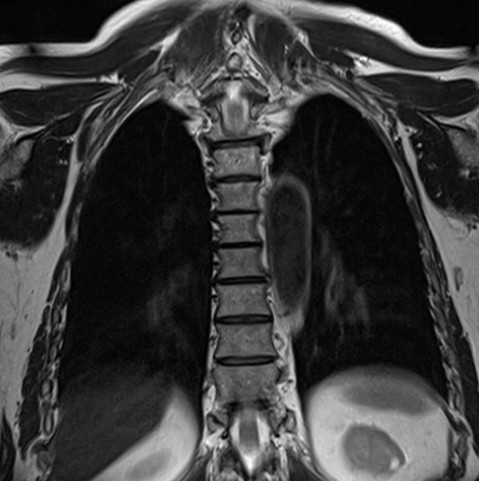

В ходе сканирования получают серию снимков в аксиальной, саггитальной и фронтальной проекциях, что способствует точной визуализации структур позвоночника и выявлению локализации и распространенности патологического процесса.

Что показывает МРТ грудного отделаНа снимках отчетливо можно увидеть тела позвонков, нервные окончания, сосуды, спинномозговой канал, хрящи, связки, мышечные волокна.